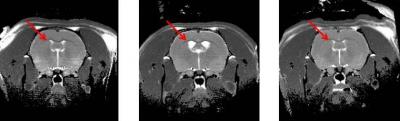

Looking at brain scans and behavior, Prof. Weiner found abnormally developing lateral ventricles and the hippocampus in those rats with "schizophrenia." Those that were at high risk for the condition could be given drugs to treat their brains, she determined. Following treatment with risperidone and clozapine, two commonly used drugs to treat schizophrenia, brain scans showed that the lateral ventricles and the hippocampus retained a healthy size.

"Clinicians have suspected that these drugs can be used to prevent the onset of schizophrenia, but this is the first demonstration that such a treatment can arrest the development of brain deterioration," says Prof. Weiner. She says that the drugs work best when delivered during the rats' "adolescent" period, several months before they reached full maturity.